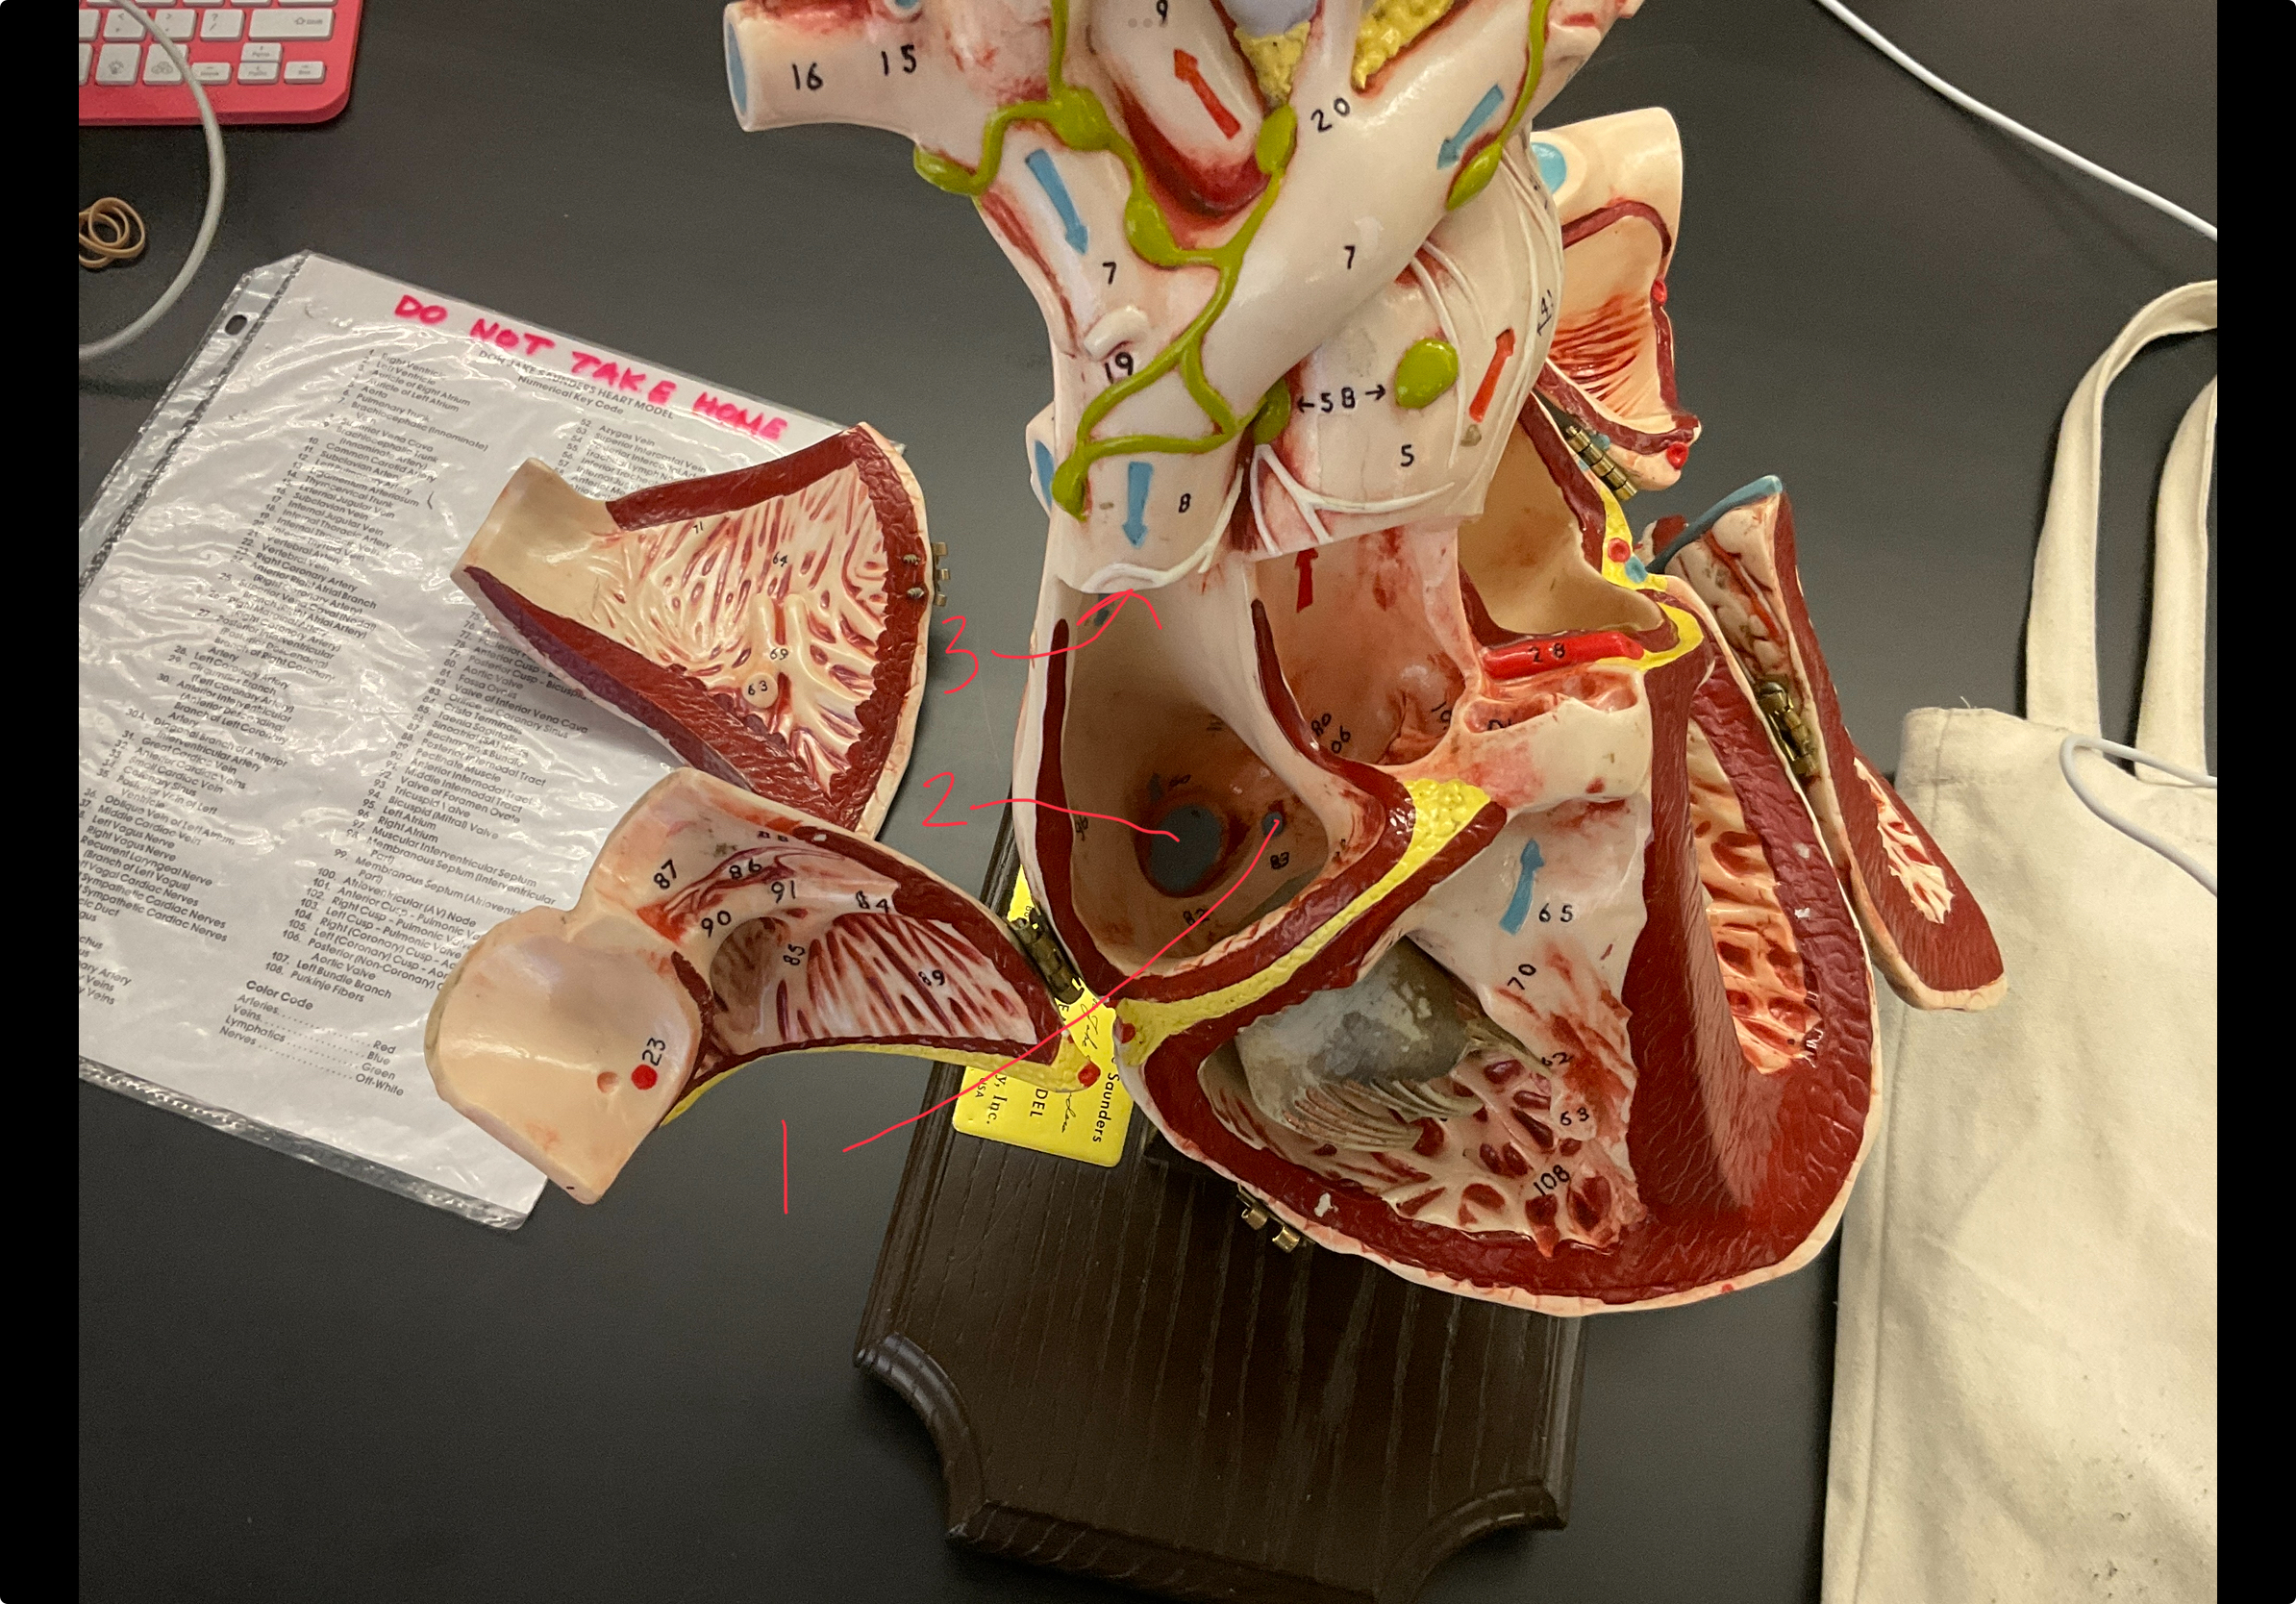

1

epicardium

2

3

endocardium

3

2

myocardium

4

1

coronary sinus

5

2

inferior vena cava

6

3

superior vena cava

7

1

right ventricle

8

2

left ventricle

9

3

bicuspid

10

4

tricuspid

11

5

interventricullar septum

12

6

left atrium

13

7

aorta

14

8

aortic trunk

15

9

pulmonary semi-lunar valve

16

10

atrevoventricullar sulus

17

11 (not smooth part)

trubeculae carneae

18

1

papillary muscle

19

2

chordae tendineae

20

4

pulmonary trunk

21

6

aortic trunk

22

aortic semi lunar valve

New cards

anterior inter ventricular sulcus